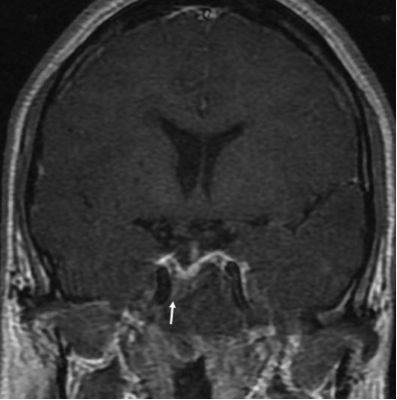

- МРТ головного мозга с внутривенным контрастированием: МР-признаки полиоссальной фиброзной дисплазии (см. описание). Умеренный экзофтальм. Умеренное расширение конвекситальных субарахноидальных пространств. МР — данных за очаговые изменения вещества головного мозга не получено (рис. 13, 14).

Рис. 14. Пациентка Щ. МРТ головы. Фиброзная дисплазия тела клиновидной кости с облитерацией задней части клиновидных пазух.

Описание. Гипофиз деформирован, имеет вогнутый верхний контур, размеры: вертикальный — 4,5 мм, поперечный — 16 мм, переднезадний — 12 мм. Структура аденогипофиза однородна, воронка расположена по средней линии, задняя доля гипофиза имеет типичный сигнал и локализацию.